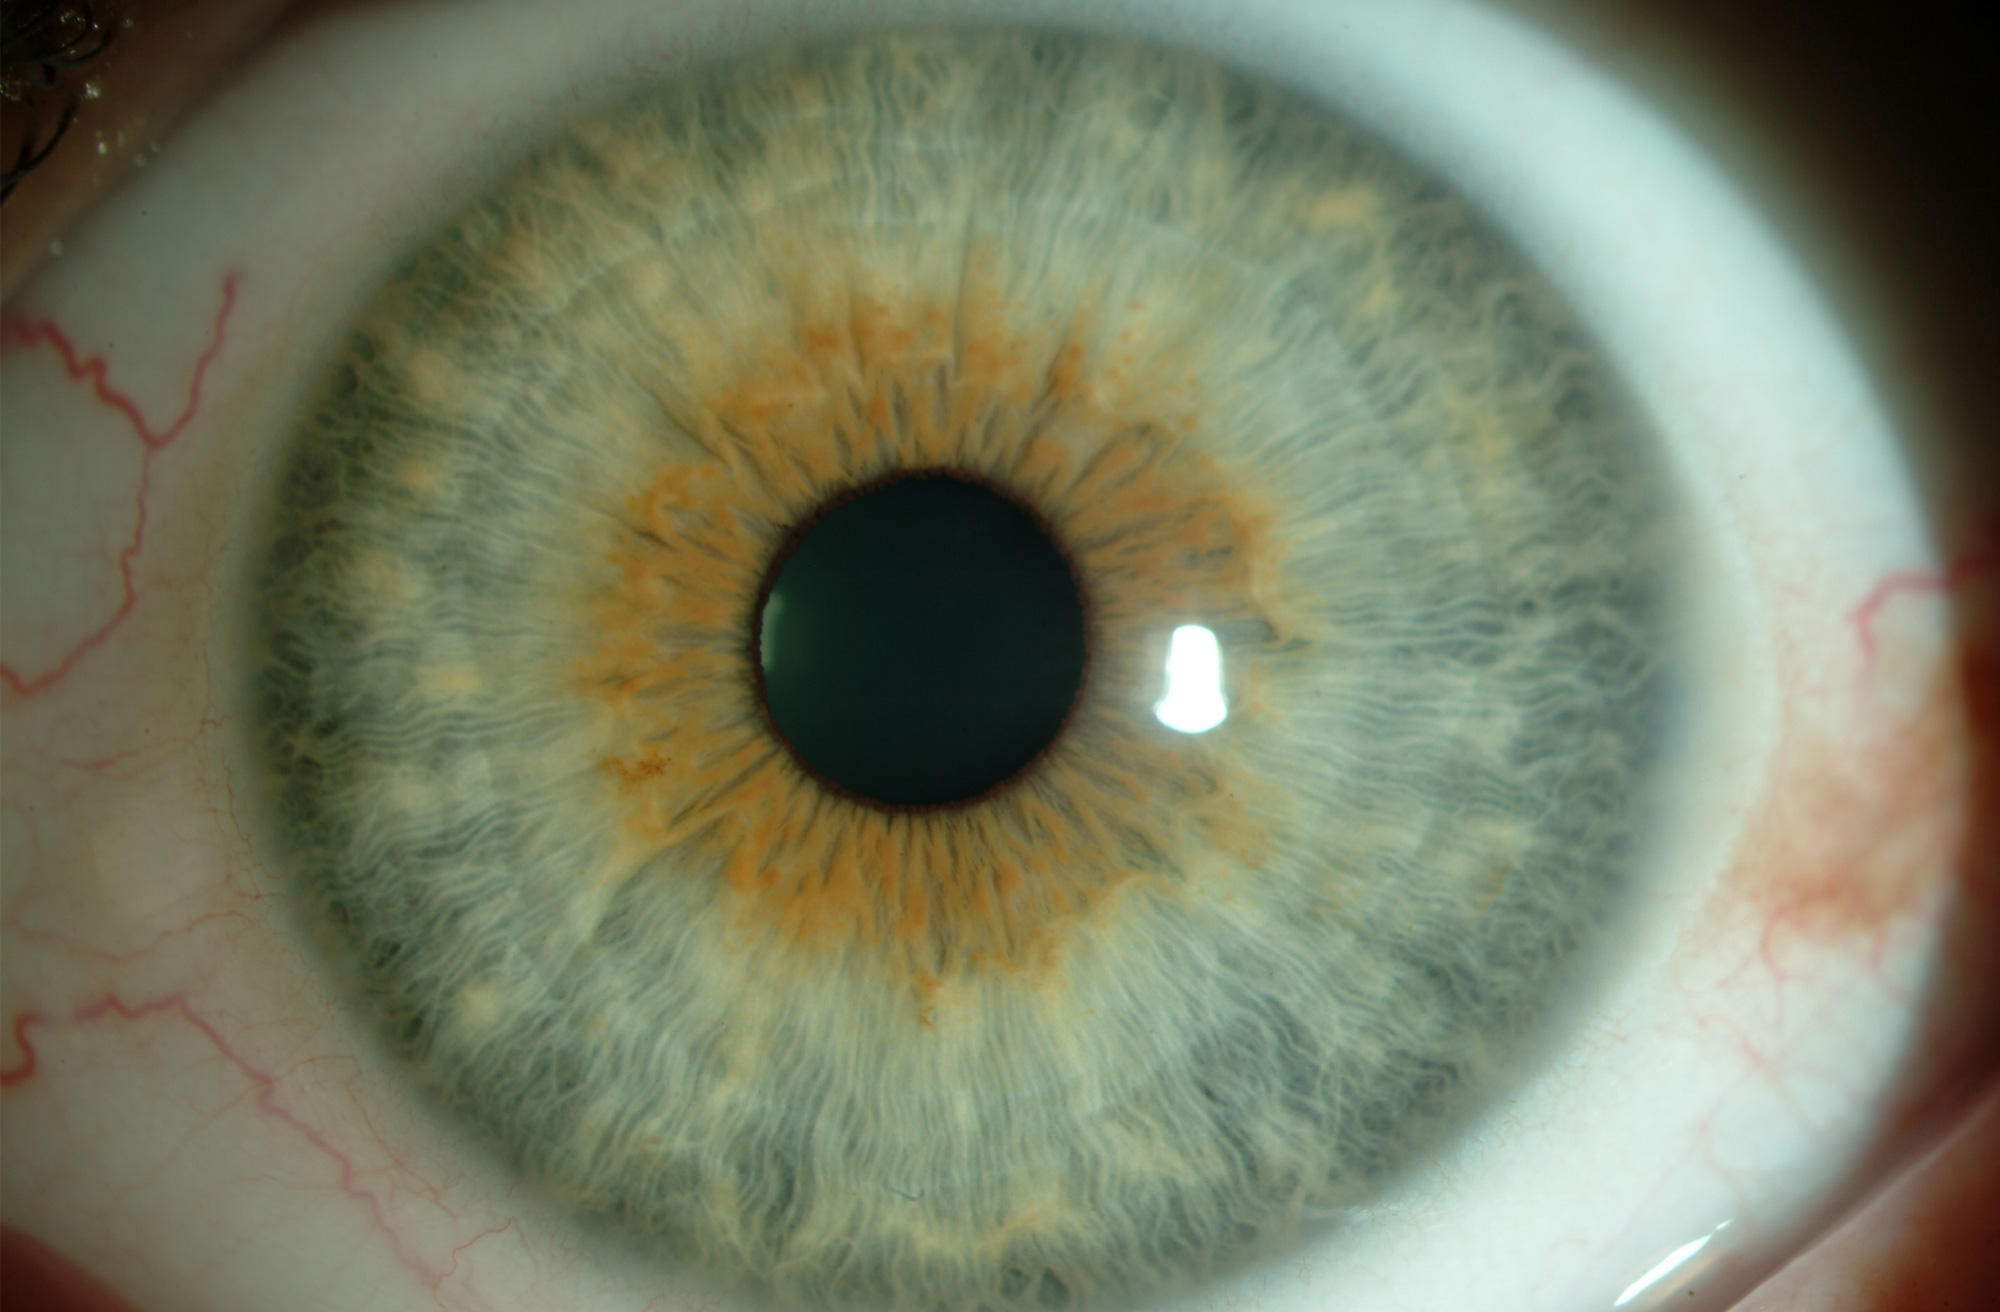

Consiste en realizar con una apertura en el iris que permita el paso de humor acuoso de atrás hacia delante en caso de bloqueo pupilar, evitando un aumento de la presión intraocular.